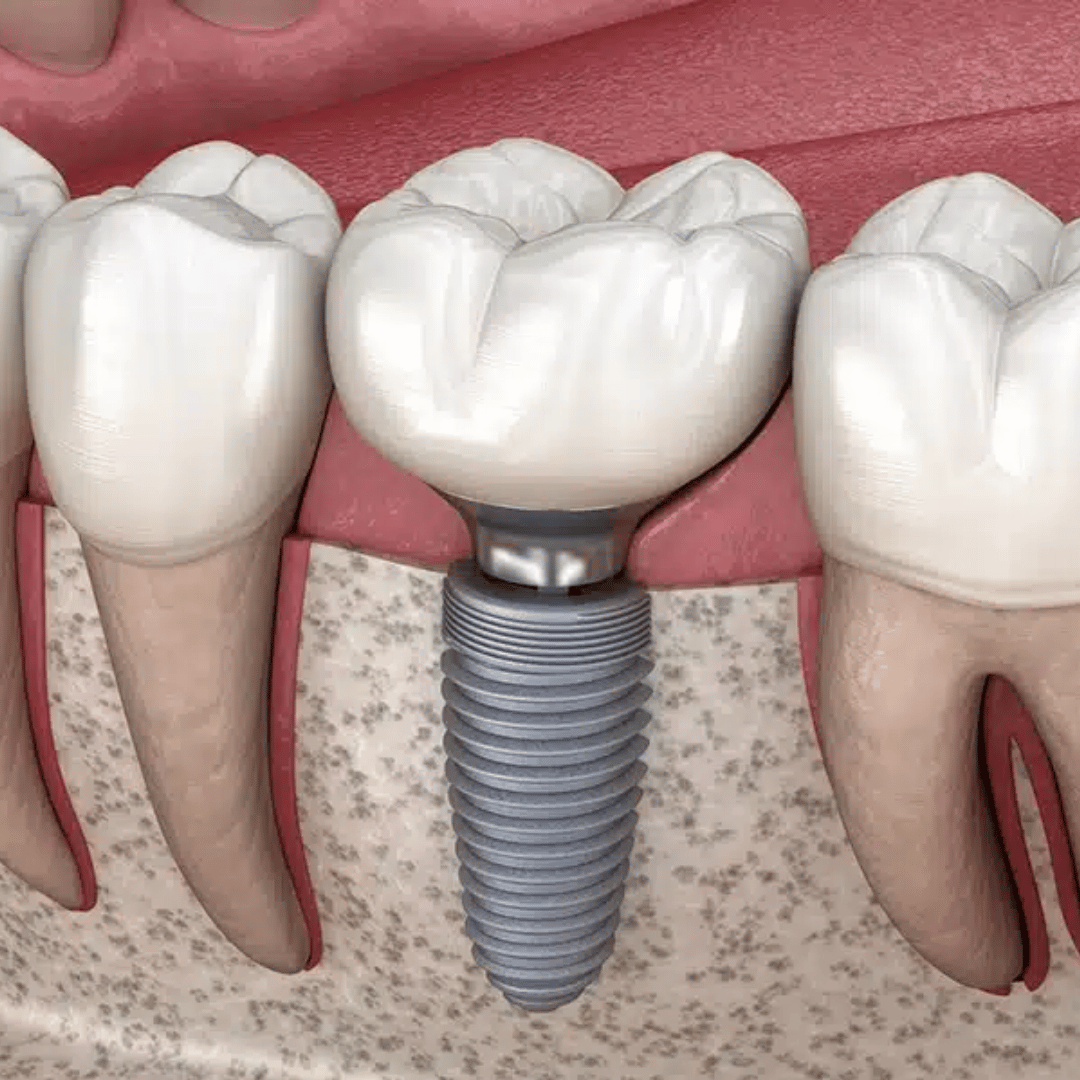

Dental Implants

Permanent, natural-looking replacement teeth that let you chew and smile with confidence.